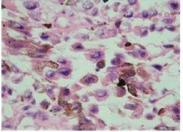

• 肺假性淋巴瘤

628健康網(wǎng)為您分享有關(guān)肺假性淋巴瘤的癥狀,肺假性淋巴瘤的治療方法,肺假性淋巴瘤的預(yù)防知識,肺假性淋巴瘤的癥狀圖片,肺...